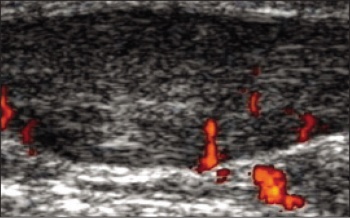

Figure 1. Longitudinal colour Doppler ultrasound of the Achilles tendon showing both hypoechoic regions and areas of neovascularisation

During surgical exploration, hyper-vascularity is present without evidence of effective healing. In fact, abnormal neovascularisation can be observed on ultrasound. Hypoechoic areas of the tendon signify regions of fibre disarray. Treatment options can be classified into conservative, injectable therapies and surgical interventions.